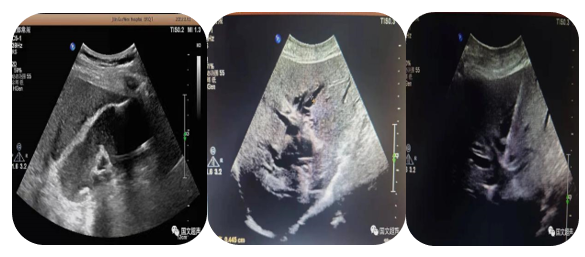

2.超聲引導(dǎo)下置管引流

超聲實(shí)時(shí)引導(dǎo)下將引流管放置在胸腹腔積液,臟器及間隙膿腫內(nèi)抽取積液減輕癥狀,亦可將藥物注入到某些特定部位從而達(dá)到治療效果。

經(jīng)皮肝膿腫穿刺引流

心包積液穿刺引流/腹腔積液穿刺引流

3.超聲引導(dǎo)下經(jīng)皮經(jīng)肝膽道置管引流、膽囊造瘺;經(jīng)皮腎造瘺、膀胱造瘺

超聲實(shí)時(shí)引導(dǎo)下將引流管放置在因腫瘤、結(jié)石等壓迫、堵塞梗阻擴(kuò)張的膽道、腎盂、膽囊、膀胱內(nèi)引流出潴留的膽汁、尿液,防止或緩解肝腎功能衰竭,進(jìn)而減緩患者痛苦為臨床爭(zhēng)取治療機(jī)會(huì)。

經(jīng)皮經(jīng)肝膽囊造瘺、膽道置管引流

經(jīng)皮腎造瘺

經(jīng)皮膀胱造瘺